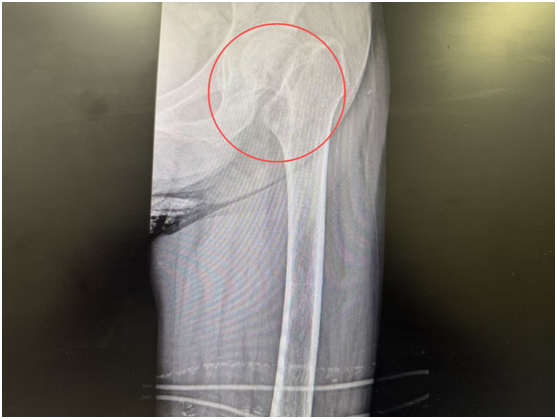

术前

入院检查结果让医生们格外揪心,除了左侧股骨颈骨折,刘奶奶还患有重度骨质疏松、2型糖尿病、双侧多发肋骨骨折(右侧3-7肋、左侧5-7肋)、陈旧性脑梗死、脑萎缩、间质性肺炎及肺结节等多种基础疾病。更棘手的是,长期卧床加上糖尿病影响,她的血糖控制不佳,肺功能也较差,给后续治疗带来了很大的麻烦。